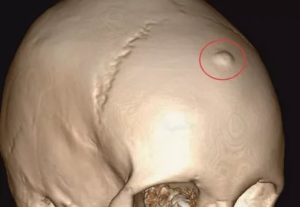

Теменная кость анатомически представляет собой парную кость мозгового отдела черепа. Остеома черепной кости – доброкачественное медленно растущее новообразование.

Остеома теменной области головы возникает в детском возрасте, протекает бессимптомно до увеличения, проявляется спустя десятки лет. Рентгенологически выглядит как неподвижное выпуклое остеогенное образование без признаков разрушения или врастания в соседние ткани. Могут возникать как в левой, так и в правой части темени. Редко локализуются в своде черепной кости.

Остеоидные остеомы теменной кости справа или слева приносят наибольший клинический дискомфорт, сопровождаются болью. При возникновении шишки на черепе рекомендуется обязательно обратиться к врачу.

Остеомы теменной кости с экстракраниальным ростом встречаются в превалирующем большинстве всех остеогенных новообразований костей черепа.

Клиника остеомы зависит от ее месторасположения. При локализации остеомы на внешней стороне костей черепа она представляет собой безболезненное, неподвижное, очень плотное образование с гладкой поверхностью.

Если остеома очень маленькая, рентген-диагностика может оказаться недостаточно информативной. Тогда дополнительно проводится компьютерная томография. 3D-реконструкция дает возможность выявить даже крошечные детали структуры остеомы, измерить размеры повреждений.